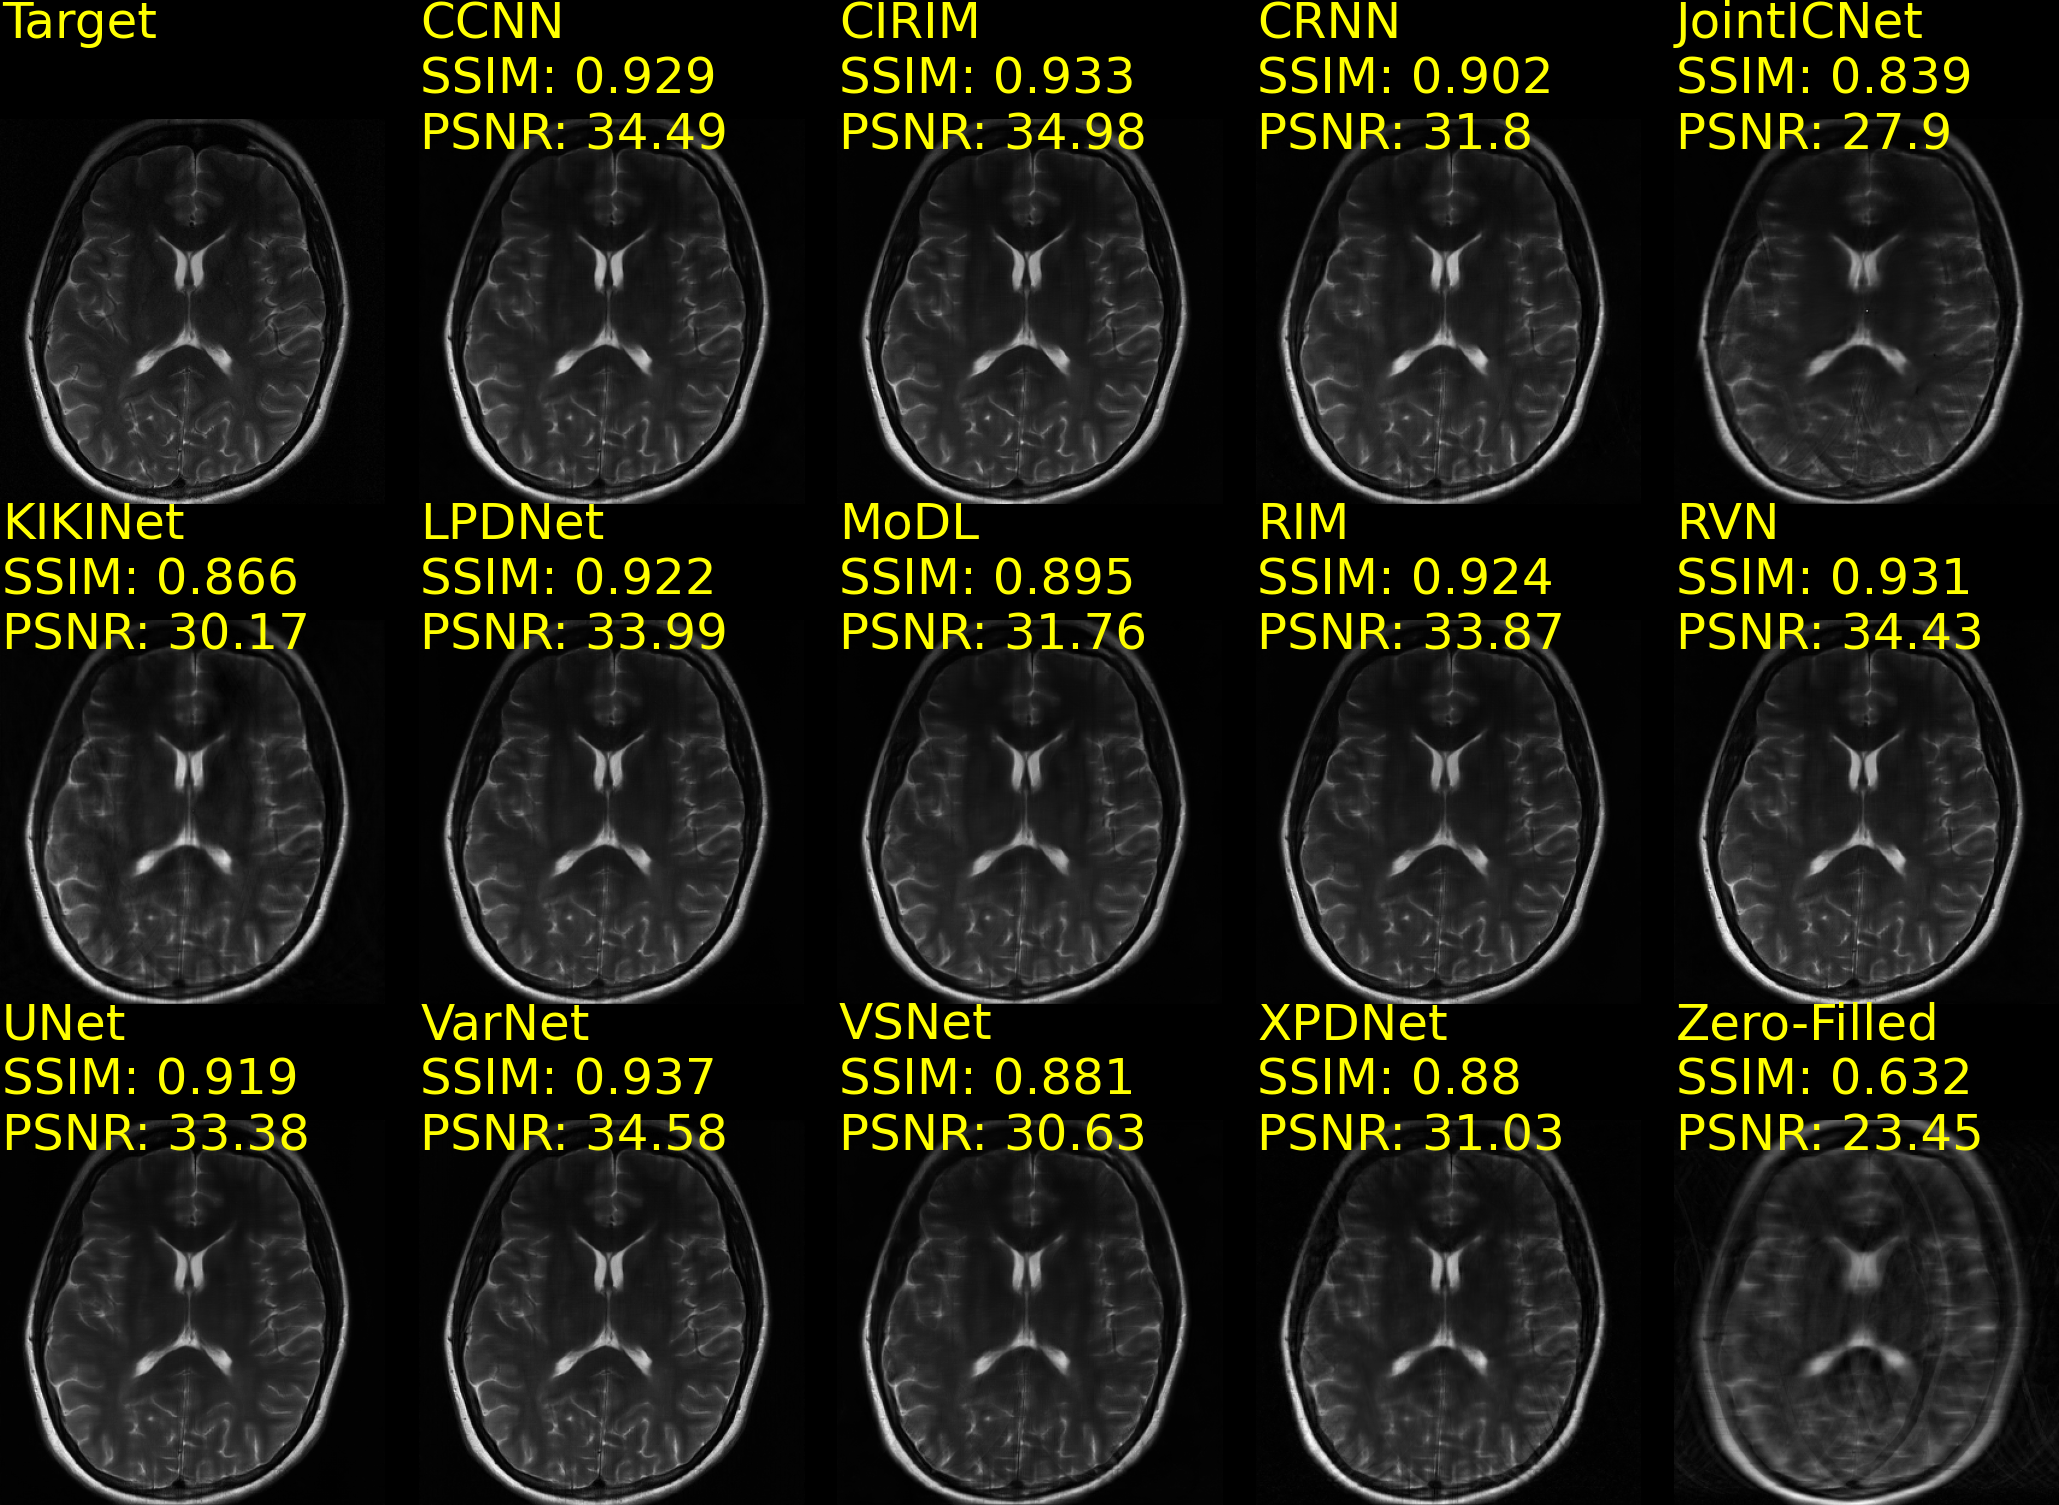

Example reconstructions of brain data are shown in Fig. 5(a) and Fig. 5(b), from the CC359 dataset, and Fig. 6(a) and Fig. 6(b), from the fastMRIBrain dataset. Figure 7 shows example reconstructions of knee data from the StanfordKnee dataset.

(a) fastMRIBrains 14-coil data - 4x acceleration

Refer to caption

(b) fastMRIBrains 14-coil data - 8x acceleration

Figure 6: Reconstructions of 14-coil T2-weighted data from the fastMRI Brains dataset, undersampled with an Equispaced 1D sampling pattern for 4x (Fig. 6(a)) and 8x (Fig. 6(b)) acceleration. The top row-first column shows the ground truth (Target) image. SSIM and PSNR scores are reported for each method and computed against the Target image. Methods are sorted alphabetically.